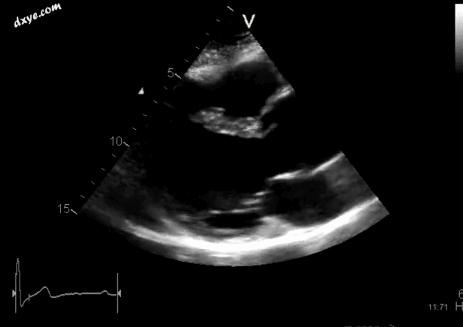

Marfan综合征患者的超声波,显示扩张的主动脉根部

MFS的诊断标准于1996年在国际上达成一致。[29]诊断基于家族病史以及在一个人群中发生的一般人群中罕见的疾病的主要和次要指标的组合 - 例如:在另一个身体系统中具有一个或多个体征的四个骨骼体征,例如眼睛和一个人心血管疾病。 MFS可能导致以下情况,但也可能发生在没有任何已知潜在疾病的人群中。